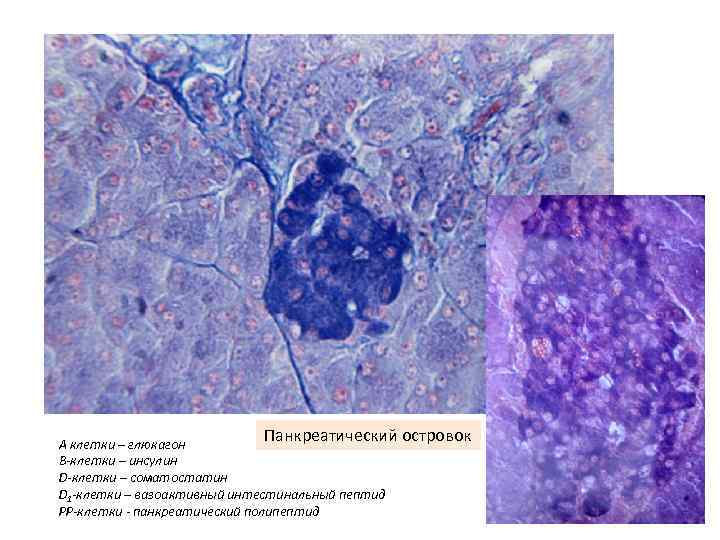

Панкреатический островок А клетки – глюкагон В-клетки – инсулин D-клетки – соматостатин D 1 -клетки – вазоактивный интестинальный пептид РР-клетки - панкреатический полипептид